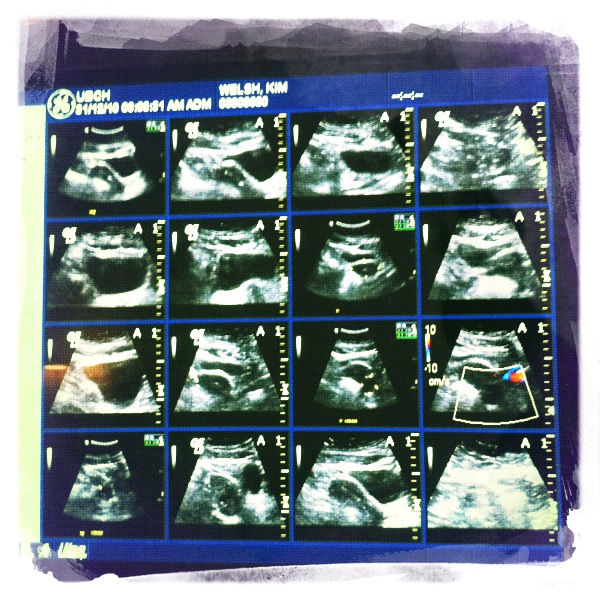

Despite my worrying and liberal interpretation of the speed limit, I managed to make it to the hospital exactly on time. It was only a few minutes before I was in a private room with my pants down around my bum; a woman marinating me in cold jelly so she could take a look around. After taking some pictures, she explained that my bladder was barely full enough – are you fucking kidding me? I was swimming – which MIGHT yield enough information as to what’s going on in my hoohah, but to be safe I could also opt for the inter-vaginal ultrasound bonus pack. Feeling brave because there was no audience (and because I just want this over with), I agreed to the Vag Cam and was rewarded with a trip to the bathroom to relieve my tricky bladder. Hooray!

I partially disrobed and rerobed in the hospital’s finest, and went back into the room. The internal camera was a long tube covered in latex and lube, which I was to insert myself (which, needless to say, I was really good at). She wiggled it around and took pictures (I assume – I had no real idea what was going on), then left me to get dressed while the radiologist looked at the pictures. After a few minutes, she dismissed me to the Urgent Care Center where I could sit and await my results.

This was the worst part of the morning, because I sat around the clinic for over an hour before the doctor got to me. Dr. Jolly went over the paperwork he was sent from radiology, and told me they found .. nothing. As far as pelvises go, mine was unremarkable (which for once is good). There were no lumps or eggs clogs or mysterious babies up in anything; my girl junk is totally awesome. The Weapon of Sperm Destruction is where it should be and has not developed artificial intelligence – I’m fine. Of course, none of that explains why I’ve been experiencing Random Wombat Pain, so they’ve referred me to a vagina specialist. My Eventual Pee indicated a high white cell count, which could indicate a symptom-free UTI; something easily cleared up with drugs. I’ll call for the appointment on Tuesday, and in the meantime .. well, it’s New Year’s Eve. I think I’ll celebrate my excellent vagina and toast to a good 2011 for all.

Wait…are those pics of the inside of your vaj-j?

Technically it’s my womb I guess :D baby free!